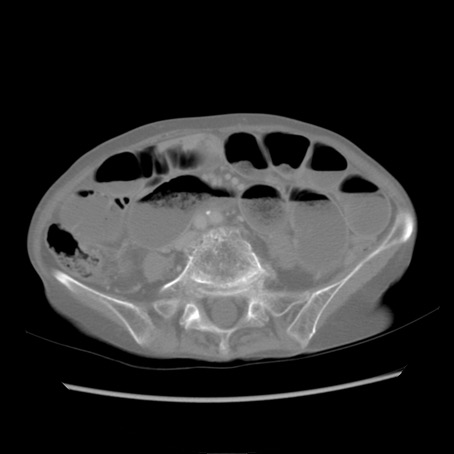

冠状断像

【症例】80歳代女性

【主訴】胸のつかえ感

【現病歴】約9時間前に食後から胸のつかえた感じあり、嘔吐あり、来院。

【既往歴】胃癌(全摘)、胆摘、虫垂炎

【身体所見】心窩部に圧痛あり、反跳痛なし。

【データ】WBC 5700、CRP 0.05